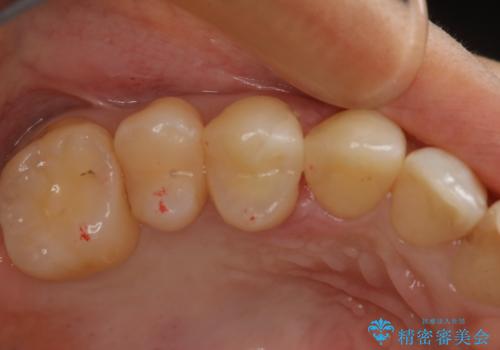

変色した詰め物の再治療 セラミックインレー

- 以前保険で治療した詰め物の変色を治したいとの主訴でご来院されました。

審美性と耐久性に優れたセラミックインレーで治療しました。

セラミックは素材の色調が歯に近く経年的な変色もないため、長期の審美性維持が可能となります。

歯の一部が虫歯になってしまった場合の治療法のひとつにインレーがあります。

虫歯になってしまった部分を含めて詰め物用に形を削り整え、型取りをし、出来上がってきた技工物をセメントで接着します。

自費治療では強度・色調・耐久性に優れたセラミックを使用した治療を選択する方が多いです。